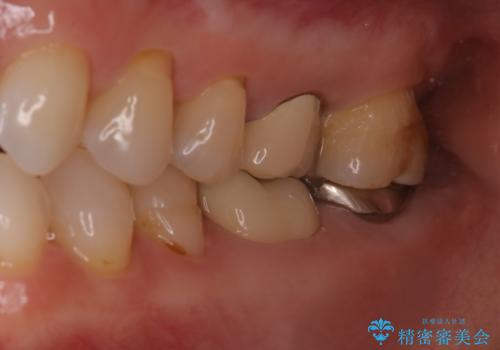

他院で仮歯までしたが、放置していたためセラミック入れたい セラミック治療

- 他院で、仮歯にしたがセラミックの値段が高すぎると思ったため治療相談も含めて来院された患者様です。

仮歯を新調させていただき、再度虫歯治療を行なって、歯の形を作りセラミックを入れさせていただきました。

フルジルコニアクラウン 7万円(税抜)

仮歯 1万円

にて治療させていただきました。色に関しても喜んでいただき満足されていました。